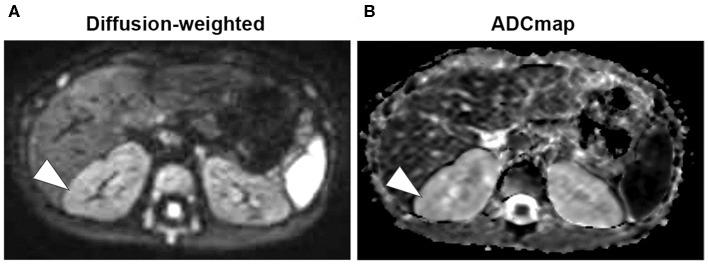

Autosomal dominant polycystic kidney disease (ADPKD) is the most common genetic disease causing renal cysts. Reports on kidney cyst infection in children are rare despite cyst infections being important complications of ADPKD. Here, we report a case of a child without any medical history who had a urinary tract infection with sepsis at 7 months. Leukocyturia persisted despite antibiotic therapy because the infection was treatment-resistant. Initial ultrasound and contrast computed tomography were inconclusive because cysts could not be detected clearly, and a family history of renal cysts was not determined. Subsequently, history of paternal renal cysts, thick walls in infectious cystic lesions on diffusion-weighted magnetic resonance imaging (MRI), and multiple small lesions with high signals on T2-weighted imaging in both kidneys became apparent. Upon diagnosis of ADPKD with cyst infection, antibiotic therapy was switched from cefotaxime to trimethoprim/sulfamethoxazole to achieve better cyst penetration, which successfully resolved the infection. In this patient, MRI was effective for clear visualization and diagnosis of infectious lesions and small cysts in undiagnosed ADPKD with cyst infection. Administering antibiotics with better cyst penetration is important. Trimethoprim/sulfamethoxazole is an option for use in children. This is the first case report that describes ADPKD with cyst infection in an infant in detail.

常染色体显性多囊肾病(ADPKD)是导致肾囊肿的最常见遗传性疾病。尽管囊肿感染是ADPKD的重要并发症,但关于儿童肾囊肿感染的报道却很少。在此,我们报告一例7个月大的无任何病史的儿童,其患有尿路感染并伴有败血症。尽管进行了抗生素治疗,但白细胞尿仍持续存在,因为该感染具有耐药性。最初的超声和增强计算机断层扫描结果不明确,因为囊肿无法清晰检测到,且未确定肾囊肿家族史。随后,父亲的肾囊肿病史、扩散加权磁共振成像(MRI)上感染性囊性病变的厚壁以及双肾T2加权成像上多个高信号小病变变得明显。在诊断为ADPKD合并囊肿感染后,抗生素治疗从头孢噻肟改为甲氧苄啶/磺胺甲恶唑,以实现更好的囊肿穿透,从而成功解决了感染问题。在该患者中,MRI对于清晰显示和诊断未确诊的合并囊肿感染的ADPKD中的感染性病变和小囊肿有效。使用具有更好囊肿穿透性的抗生素很重要。甲氧苄啶/磺胺甲恶唑是儿童使用的一种选择。这是第一例详细描述婴儿ADPKD合并囊肿感染的病例报告。